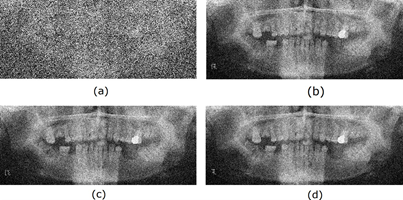

Finally, the radiological images restored using different adaptive filters are presented. Figures 6, 7, 8, and 9 show the noisy and restored images using different 2D adaptive filtering algorithms, respectively. From visual observation, it can be seen that the proposed filter produces a smoother version of the image and, thus, a slightly higher noise reduction compared to the LMS and 2D-NLMS algorithms. Furthermore, the proposed filter improves the visualization of the elements present in the image by more accurately highlighting transitions or edges. This enhancement means that details and structures of interest in the image become more discernible and can be appreciated with greater clarity.

Figure 3 shows the radiological images used for the simulation. These images are available in an open-source database [9]. The access path to the images is as follows: DentalPanoramicXrays.zip → Images → 1.png, 29.png, 58.png, 116.png.